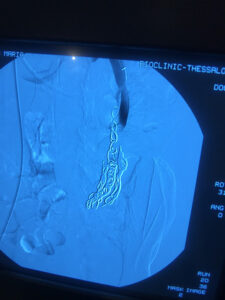

Η θεραπεία εκλογής για το σύνδρομο πυελικής συμφόρησης είναι η ενδαγγειακή αποκατάσταση με τη χρήση ελασμάτων (coils). Ουσιαστικά, πρόκειται για μια ελάχιστα επεμβατική μέθοδο, που αποσκοπεί στην κατάργηση των προβληματικών φλεβών με αρκετά ικανοποιητικά αποτελέσματα. Πρόσφατα, δημοσιεύτηκε στις κατευθυντήριες οδηγίες της Αγγειοχειρουργικής κοινότητας και στο Αμερικάνικο φλεβολογικό Forum, ως προτεινόμενη θεραπεία για την αντιμετώπιση της νόσου , η ενδαγγειακή αποκατάσταση με εμβολισμό.

case 1

φλέβας με ύφεση συμπτωματολογίας